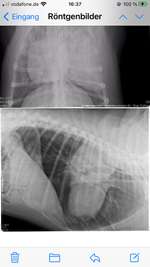

Mandelentzündung oder doch etwas anderes?

Meine 9 Monate alte fr.Bulldogge hat seit einer Woche Nasenlaufen, Probleme beim schlucken, erbrechen ( visköser schleim mit leicht blutiger Farbe ) und Abgeschlagenheit. Er nimmt nun seit 4 Tagen Antibiotika aber wir sehen keine Verbessrung. Er isst mittlerweile kaum bis nichts mehr, und ...